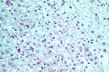

Core antigen in hepatocyte

Fig 96 - Core antigen in hepatocyte: At difference with surface antigen It is present in the nuclei of hepatocyte. Here the virus replicates and acquires the envelop of surface antigen in the cytoplasm.